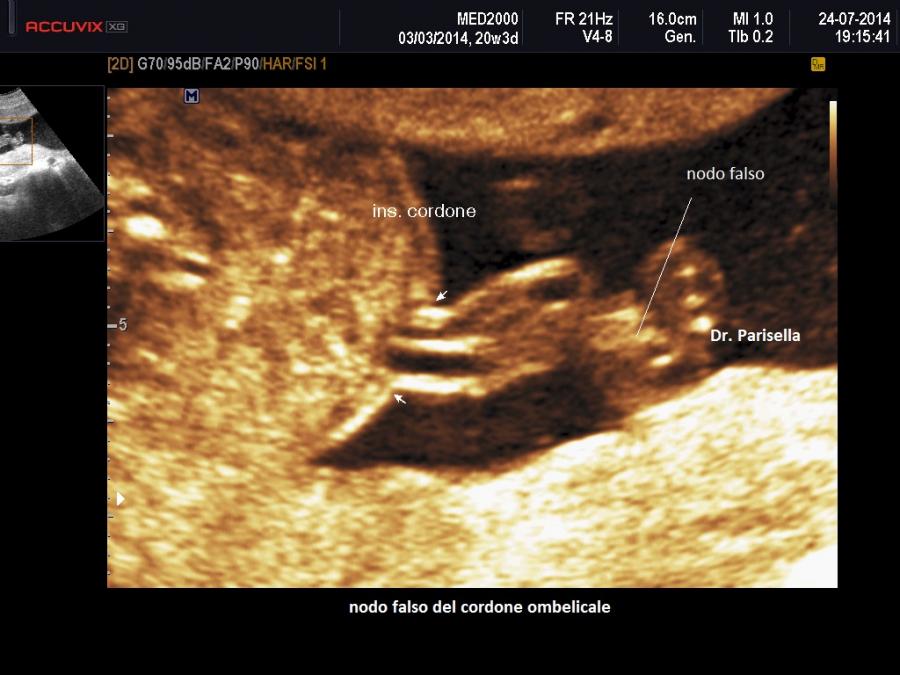

Nodi, giro di cordone attorno al collo, aggrovigliamento del cordone: I nodi del cordone ombelicale possono essere classificati in due tipi: i nodi veri e i nodi falsi. I nodi veri sono determinati dal passaggio del feto entro un'ansa del cordone stesso, generalmente a causa di una eccessiva lunghezza del cordone ( normalmente il cordone ombelicale ha una lunghezza a termine di circa 50 cm.); hanno una prevalenza di 1:100 gravidanze e un fattore predisponente è il polidramnios.  Normalmente la normale quantità di gelatina di Warthon e la pressione idrostatica dei vasi ombelicali impediscono che il nodo si serri completamente, ma quando la gelatina di Warthon diminuisce o si ha una riduzione della pressione artero-venosa del circolo fetale questi tipi di nodi possono restringersi determinando lo strozzamento dei vasi ombelicali e la conseguente asfissia del feto. Il vero nodo del cordone ombelicale spesso non viene scoperto nel periodo prenatale perché non è associato a un segno clinico o ecografico intrauterino caratteristico. E’ stata descritta la possibilità di fare diagnosi col cosiddetto “segno del cappio sospeso”: una sezione trasversale del cordone ombelicale circondata da una immagine ad anello di cordone ombelicale (Lopez R. et al., 2004). Vari autori comunque riportano che i rari casi  di diagnosi prenatale ecografica di nodo vero segnalati in letteratura non hanno nessun valore predittivo. I nodi falsi invece sono determinati da anse formate dai vasi ombelicali all'interno del cordone stesso; queste anse dei vasi ombelicali sono tenute "fisse" in tale posizione viziata da addensamenti di gelatina di Wharton attorno ad esse. In pratica la gelatina di Wharton, che normalmente protegge i vasi ombelicali, in questo caso, addensandosi attorno ad essi, ne provoca la fissità del loro decorso anomalo. Al color doppler è possibile osservare i normali flussi attraverso i vasi ombelicali compresi nel nodo. I nodi falsi in genere non rappresentano alcun pericolo per il feto. Il riscontro di nodi del cordone è il  più delle volte un reperto inatteso al momento del parto e l’incidenza è intorno all’1%. I fattori associati sono la maggiore lunghezza del cordone e la multiparità. Il nodo falso (ridondanza locale dei vasi del cordone) non riveste alcun significato clinico.